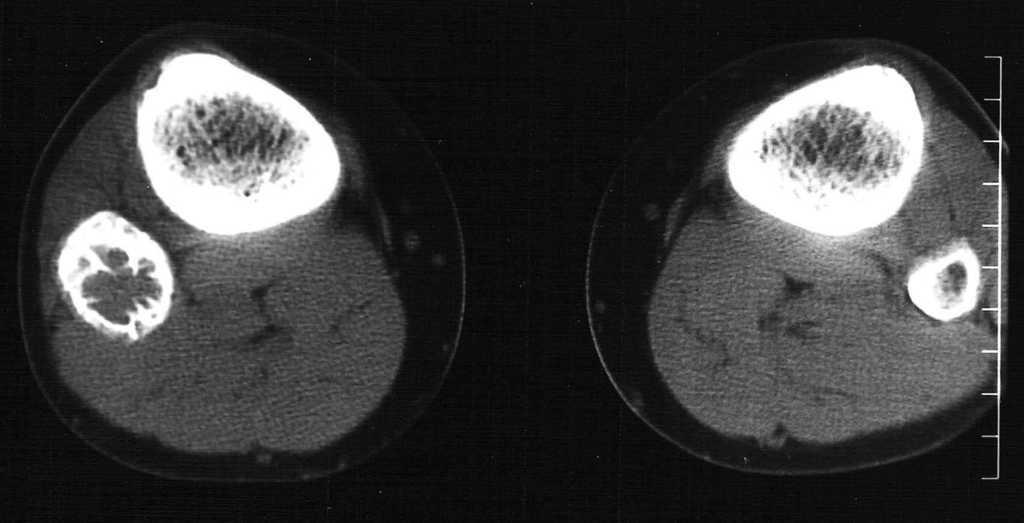

Paciente varón de 15 años, que fue remitido a consultas de traumatología por genu valgo. No tenía antecedentes de interés, salvo crisis asmáticas en la infancia, y la presencia de una lesión lítica ya conocida en el peroné, que sugería el diagnóstico diferencial de displasia fibrosa o quiste óseo aneurismático como primeras posibilidades. La lesión parecía haber crecido respecto a estudios previos. En la radiografía simple (fig. 3), se identificaba una gran lesión lítica expansiva que afectaba predominantemente a la metáfisis proximal del peroné derecho, extendiéndose caudalmente a la diáfisis, y limitada superiormente por la placa de crecimiento. No tenía matriz ósea interna y la zona de transición, al menos en la zona inferior, era estrecha. En el interior presentaba un patrón de múltiples septos con cierto adelgazamiento endostal. En la TC (fig. 4) la cortical estaba muy adelgazada, con focos de discontinuidad sin identificar masa de partes blandas, y presentaba finos septos internos. Se realizó un estudio mediante RM con un equipo de 1,5T (Gyroscan Philips Intera). En la RM el tamaño aproximado de la lesión era de 8,5 x 3,3 x 3 cm (craneocaudal x anteroposterior x lateromedial). La lesión insuflaba el peroné sin visualizar masa de partes blandas. En la secuencia T1-ES (TR/TE 460/15) se comportaba hipointensa de forma homogénea (fig. 5). En la secuencia STIR (1688/15) (fig. 6) parecía tener dos componentes, con diferentes intensidades de señal. El superior hipointenso y el inferior levemente hiperintenso. En la secuencia dinámica T1 (TR/ TE 460/15) tras gadolinio itravenoso (figs. 7 y 8) presentaba un leve realce periférico del componente superior en fase tardía con prácticamente nulo realce en fase precoz y, sin embargo, un intenso realce del componente inferior en fase precoz, seis segundos después de que el contraste se identificase en el interior de los vasos arteriales, con realce persistente en fase tardía (fig. 9). Se realizó una gammagrafía ósea de cuerpo completo en proyecciones anterior y posterior en tres fases. En la fase vascular se observaba un incremento en la llegada del radiotrazador del pool sanguíneo a la región proximal del peroné derecho. La imagen tardía mostraba una hipercaptación en el extremo proximal de dicho hueso. Descartaba la posibilidad de quiste óseo, que no suelen mostrar captación en la gammagrafía y aconsejaban descartar otro tipo de tumoración ósea. No se visualizaron otras lesiones a distancia. En estos momentos el diagnóstico diferencial propuesto fue de fibroma condromixoide, fibroma desmoplásico y quiste óseo aneurismático, a pesar de la ausencia de niveles líquido-líquido. A continuación se realizó una biopsia abierta, con diagnóstico de fibroma desmoplásico. En el estudio macroscópico se identificaban varios fragmentos blanquecinos de consistencia ósea. En el estudio microscópico, se identificó una proliferación de células elongadas, separadas de abundantes fibras de colágeno. La densidad celular era muy variable en función del campo estudiado, lo mismo que la disposición de las fibras de colágeno, bien onduladas o con gran laxitud. Las células tenían núcleos ovoideos, sin aparentes nucleolos y sin figuras mitóticas. Algunos de los remanentes óseos atrapados en la muestra tenían actividad osteoclástica, sin ver en ningún momento atipias.

Fig. 4.--Tomografía computarizada sin contraste. Presencia de finos tabiques internos incompletos.